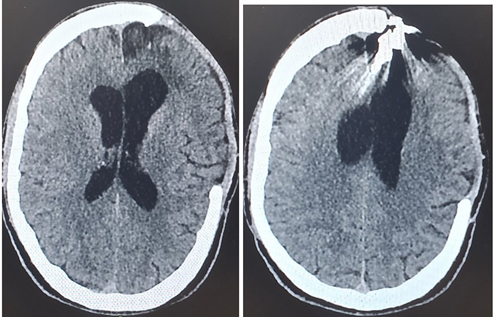

During the neurosurgical procedure, the following stages were performed: Left craniectomy, meningeal section and opening. A small puncture of the anterior part of the sagittal is found where the bleeding is successfully stopped. Wound closure in layers. He was taken under full sedation to the Intensive Care Unit (Figures 1-4, a and b).

Figure 1(a and b): CT Brain scan 24 hours (1st day) after the brain injury and the neurosurgery.